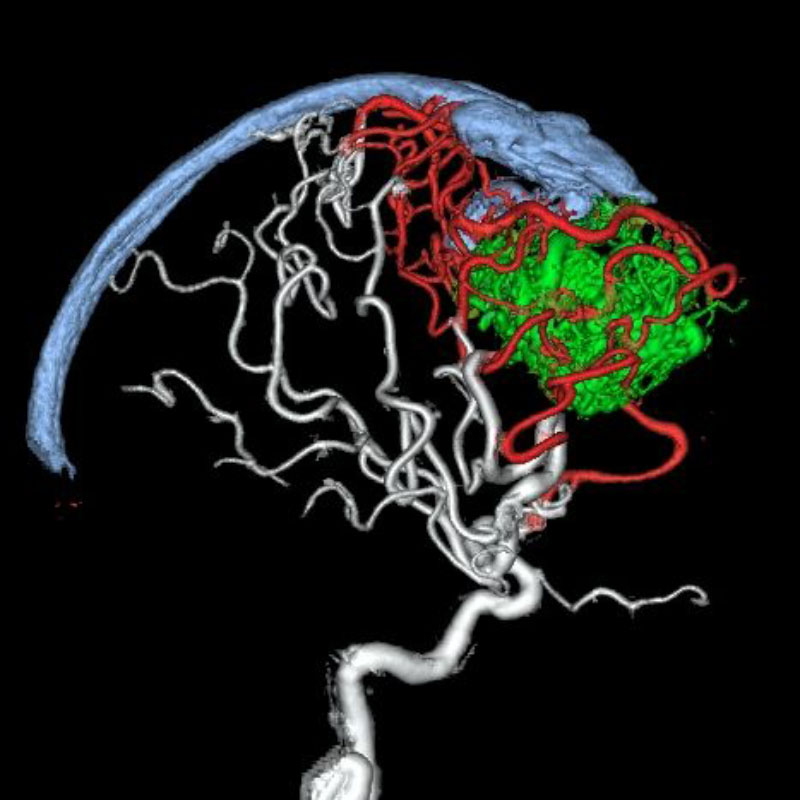

脳動静脈奇形

血管塞栓術

松田/濵田/元永